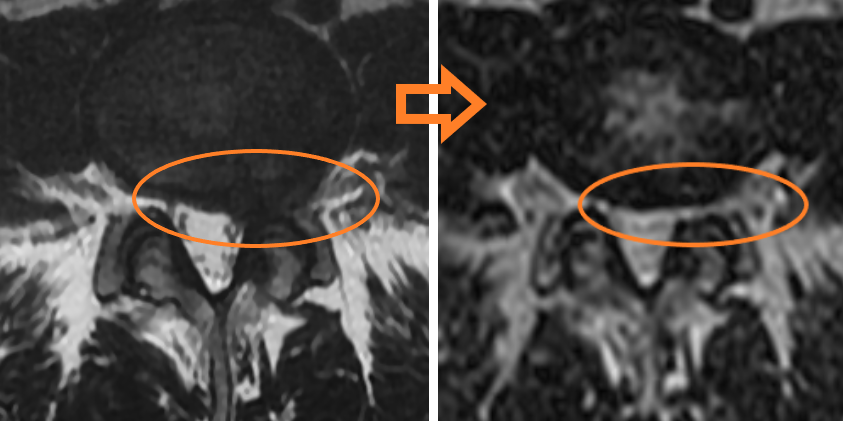

Пример резорбции грыжи диска L4-L5